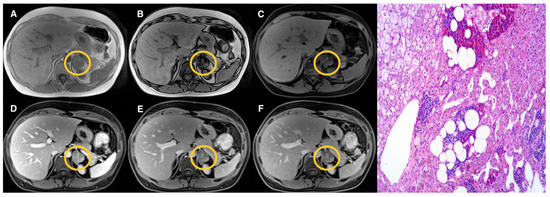

2.3. Image Analysis

3. Results